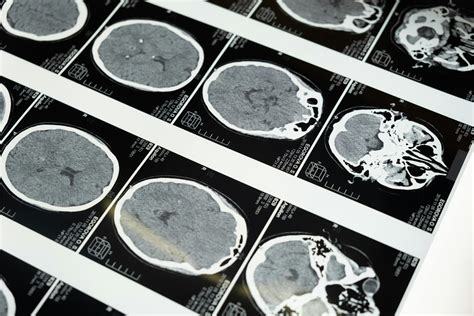

Diagnosing Chronic Microvascular Ischemic Changes

Diagnosing chronic microvascular ischemic changes involves a combination of medical history, physical examination, and diagnostic tests. Some of the common diagnostic methods include:

• Imaging Tests: Such as ultrasound, CT scans, and MRI to visualize the blood vessels and assess blood flow.